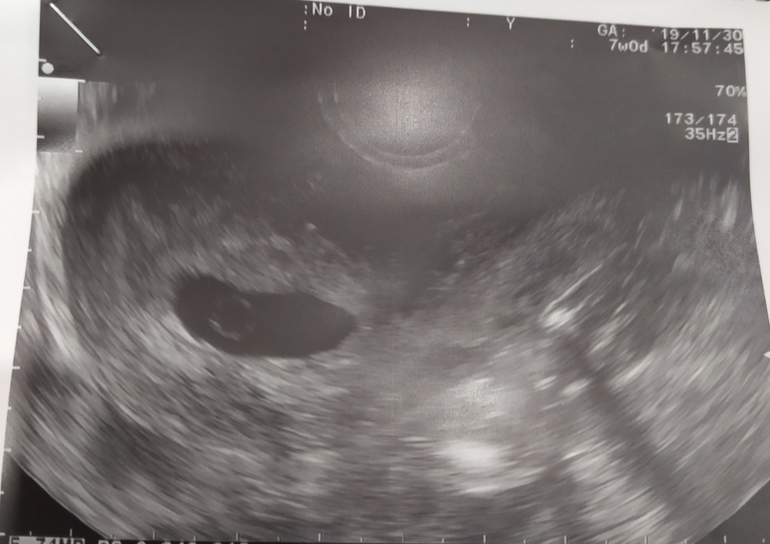

Марина, понятно, жалко, вот у меня сейчас такой же желток, правда яйцо вроде бы меньше. Опять поздняя овуляция и не понятно, когда зачатие. За 2,5 недели до этого УЗИ в матке вообще было пусто. Начиталась, что большой жм - плохой признак ((

Марина, вот вообще мне ничего не сказали, распечатку не отдали. Я пришла в жк вставать на учёт, а она мне внеплановое УЗИ без записи предложила, "пока аппарат не выключили" очень быстро посмотрела, сказала, что ей всё не нравится, срок большой (8+ акушерских), яйцо маленькое, без эмбриона и ещё гематома сзади, скорее всего замерло и начало уже отслаиваться.. но я ей не сказала, что 2 недели назад была на УЗИ и там не было ничего в матке. Надо было сказать, гиня очень торопилась просто. Я сначала успокоилась, подумала, она не знает про позднюю овуляцию. А потом посмотрела видео узистов, какой должен быть по виду жм на этом сроке и расстроилась. Он у меня большой и в центре, а " правильный" жм с краю и маленький. В общем буду ждать неделю и ещё платно сделаю. А ещё через неделю ещё раз в жк